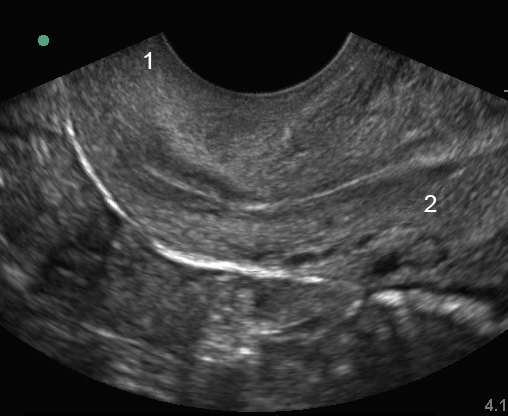

盆腔阴道内子宫:子宫下段矢状面图像

宫颈

子宫中段